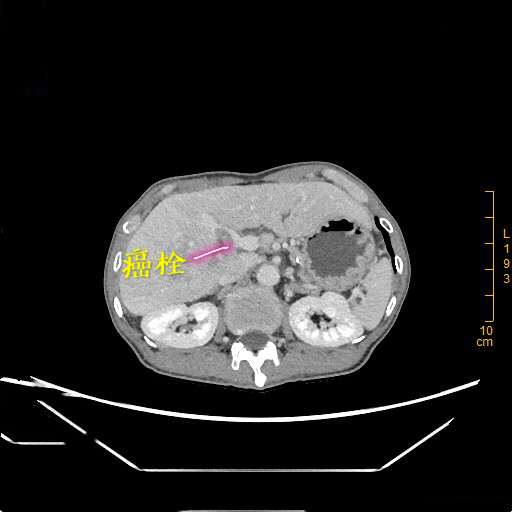

患者为65岁的老年男性,无意中发现右上腹有一个鸡蛋大小包块,偶尔会有胀痛,未予以重视,肿块进行性长大,检查提示肝脏肿物,遂到深大总院肝胆外科就诊。李晓武教授及其团队接诊后,发现患者较为消瘦,身高176cm却仅有43kg的体重,经查体发现患者包块巨大,下缘已达盆腔位置,极为罕见。进一步CT检查结果显示,患者的肿瘤已占据肝脏右叶大部分,直径达13cm,向后压迫下腔静脉,向下压迫结肠等肠管,并且伴有门静脉右支癌栓及右肝静脉癌栓形成。

一、术前利用计算机3D模拟可视化技术测算肿瘤的体积和形态、癌栓的位置、血管的走行以及切除肿瘤后剩余肝脏的体积,制定了首选手术方案及备选手术方案;